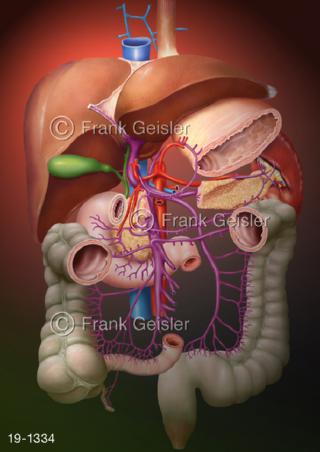

Bildergalerie Medical Art

Bilder zu Medical Art und Anatomie-Art, visuelle Darstellung medizinischer Inhalte künstlerisch umgesetzt, medizinisches Fachwissen als künstlerische Gestaltung für die Ausbildung, zur Patientenaufklärung und zur wissenschaftlichen Kommunikation, als künstlerische Dekoration in Gesundheitseinrichtungen und Arztpraxen